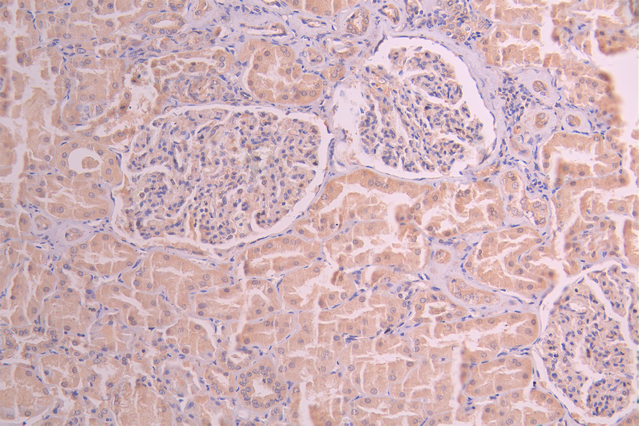

IHC image of CSB-RA440534A0HU diluted at 1:100 and staining in paraffin-embedded human kidney tissue performed on a Leica BondTM system. After dewaxing and hydration, antigen retrieval was mediated by high pressure in a citrate buffer (pH 6.0). Section was blocked with 10% normal goat serum 30min at RT. Then primary antibody (1% BSA) was incubated at 4°C overnight. The primary is detected by a Goat anti-rabbit polymer IgG labeled by HRP and visualized using 0.05% DAB.